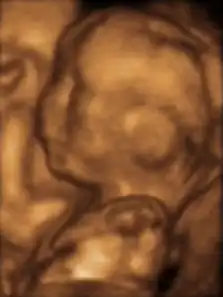

- Трёхмерное УЗИ 12-недельного плода